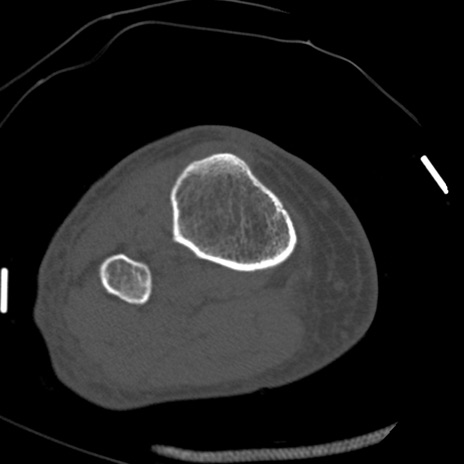

症例28 右膝関節CT(横断像)

右膝関節CT